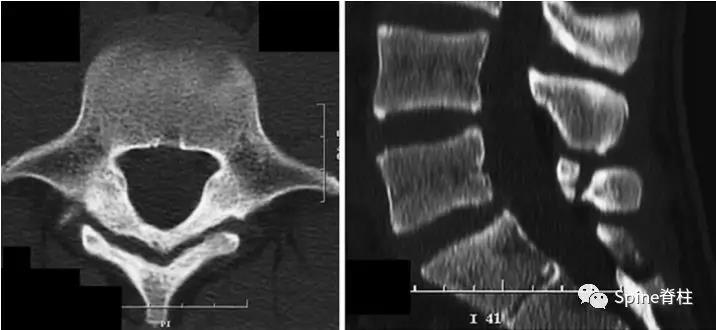

图:L5全椎板裂15岁相扑运动员,严重腰痛,后伸明显加重正侧位X线示椎板水平骨折线(白箭头)。MRI示T2椎板高信号,T1椎板低信号